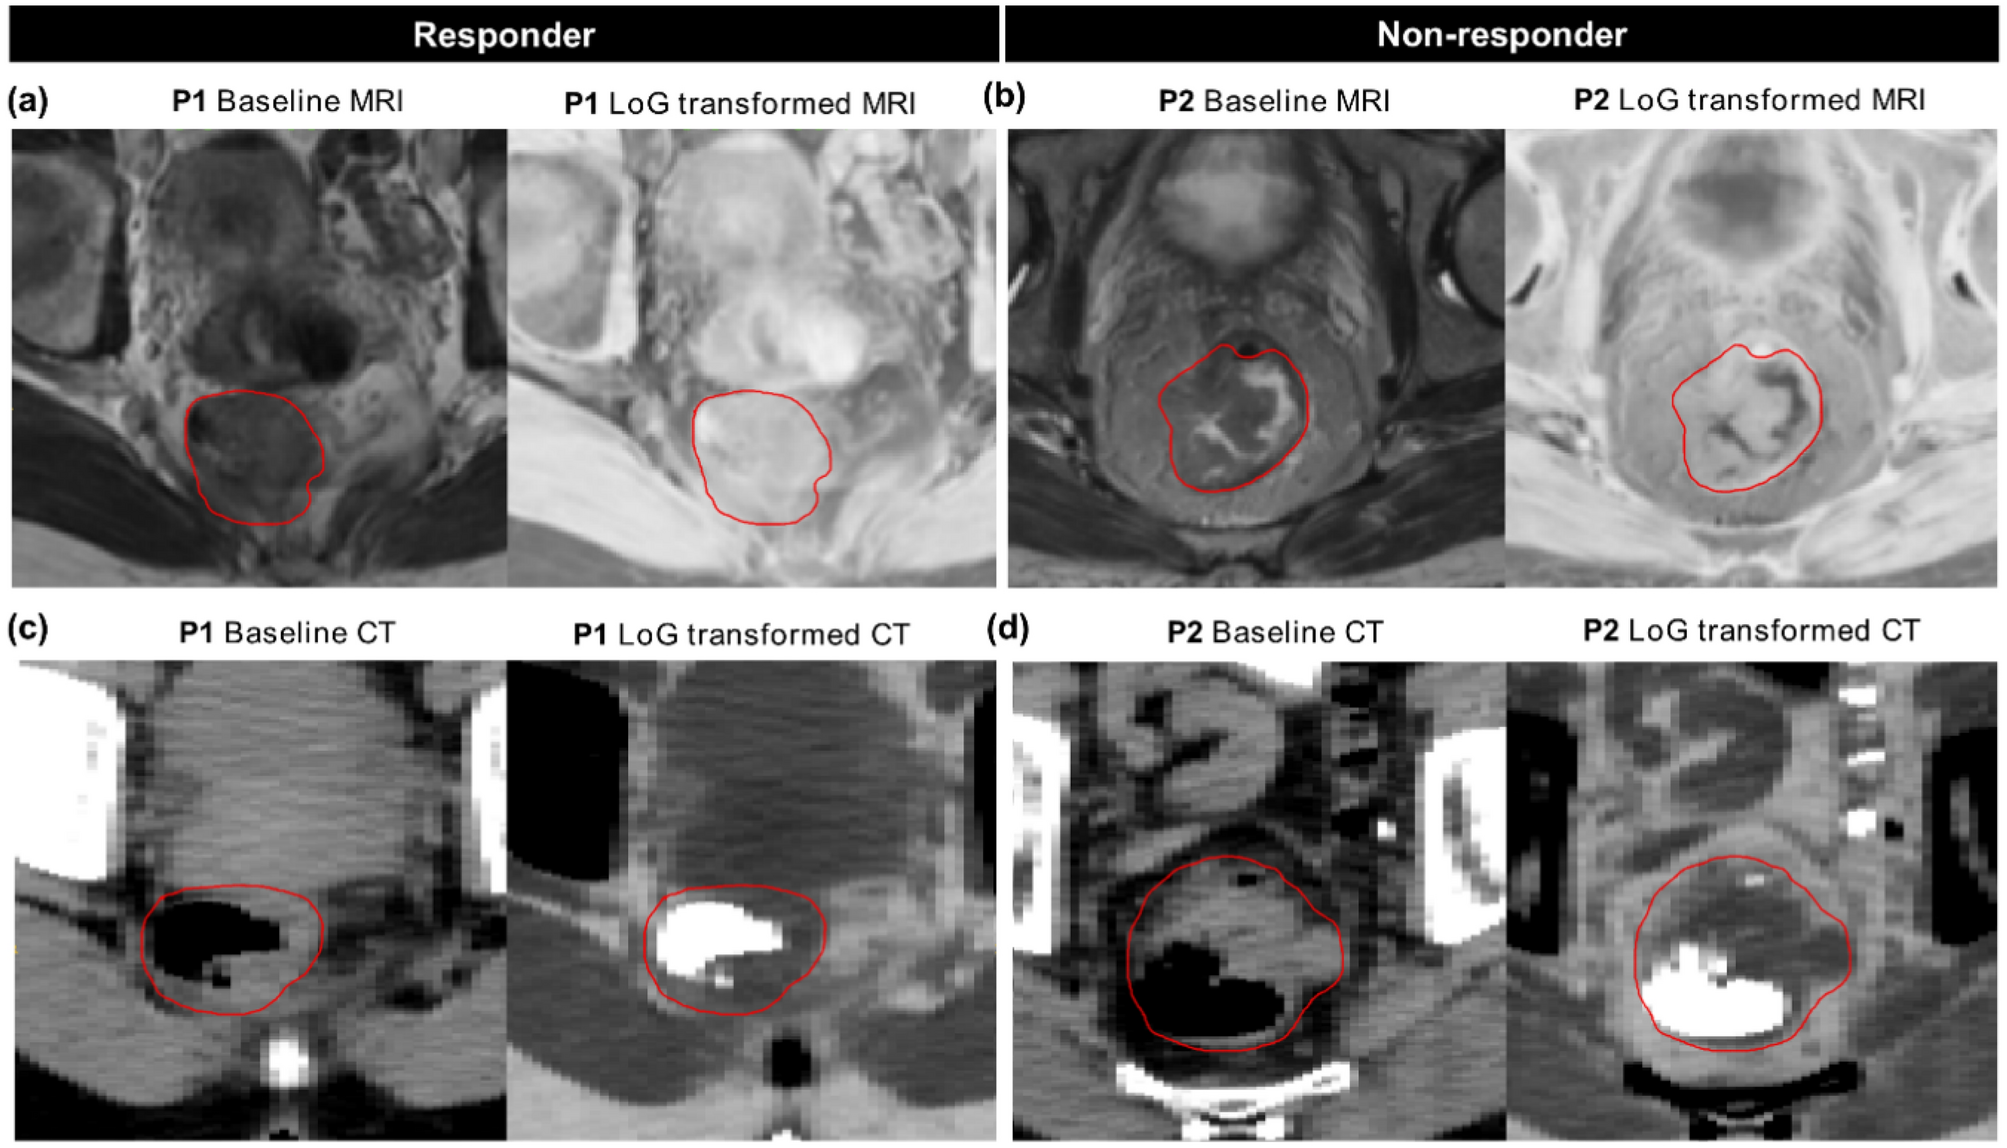

Figure 3

Representative images from MRI (a,b) and CT (c,d) with corresponding Laplacian of Gaussian (LoG) transformed images from two patients (P) in the two response groups, i.e. responder: P1 and non-responder: P2 on the training data. Red contours mark the gross tumour volume (GTV). P1 (responder: TRG = 4) showed an overall homogenous appearance on the baseline MRI. On the contrary, P2 (non-responder: TRG = 1) showed a more heterogeneous GTV with a low stat_min value on the LoG transformed MR image, which corresponds to some high pixel intensities on the baseline MRI. Similarly, a more homogenous GTV (excluding the air voxels) can be seen in P1 compared to P2 on the baseline and LoG transformed CT slices, possibly causing low gradients in the intensity histogram for the responder.